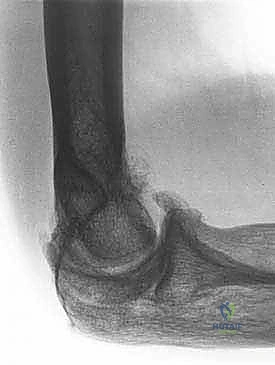

- الأشعة السينية (X-rays): لتقييم شكل العظام، البحث عن الكسور القديمة، وتحديد أماكن النتوءات العظمية والأجسام الحرة الكبيرة.

- الأشعة المقطعية ثلاثية الأبعاد (3D CT Scan): وهي الأهم قبل الجراحة. تعطي الجراح خريطة مجسمة دقيقة لكل نتوء عظمي وكل حاجز ميكانيكي داخل المفصل، مما يسهل استهدافه بالمنظار.

3. خشونة المفاصل والتهاب المفاصل التنكسي (Osteoarthritis)

مع التقدم في العمر أو الاستخدام المفرط (كما في حالة الرياضيين أو العمال اليدويين)، يتآكل الغضروف المبطن للمفصل، وتتكون نتوءات عظمية (Osteophytes) تعمل كمصدات ميكانيكية تمنع المرفق من الثني أو المد الكامل.

* التعظم غير الطبيعي (Heterotopic Ossification) حيث يتكون عظم جديد داخل الأنسجة الرخوة.